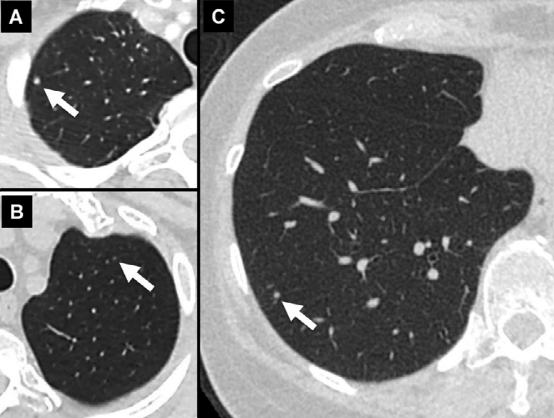

A、右肺上叶,B、左肺上叶,C、右肺下叶。3mm或更小的结节 (箭头)。

由于在确定病变是实性结节、亚实体结节还是磨玻璃结节时存在准确性和可变性的限制,因此不需要测量此类小结节。